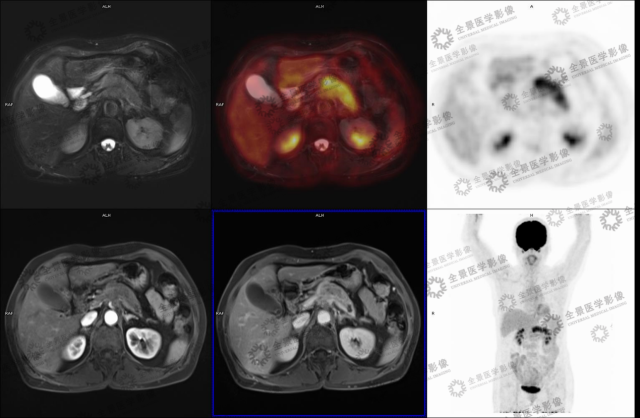

实例一

病史:女 70 岁 腹部不适,纳差半月,CT:胰腺 MT 伴小网膜囊淋巴结肿大及血管侵犯。

病灶呈延迟强化,FDG 代谢增高,考虑胰腺癌。